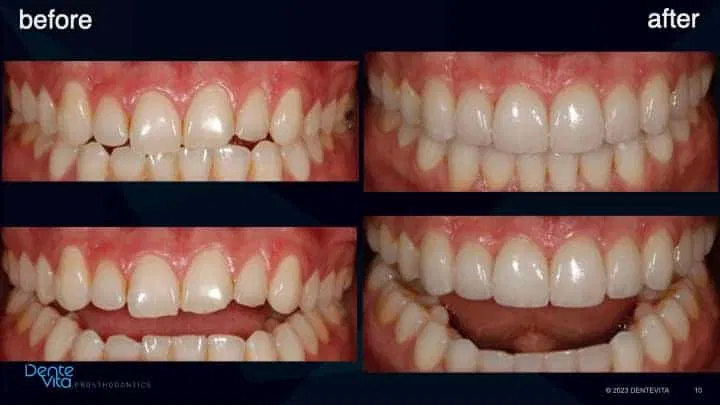

Tooth enamel wear and erosion, with resultant short/smaller teeth dimensions and associated vertical and horizontal tooth drift.

This case study addressed significant tooth erosion from gastric reflux. Lost vertical space from vertical tooth drift was reversed with orthodontic treatment (intrusion and alignment therapy).

After completion of successful orthodontic therapy, missing tooth structure was rehabilitated/restored with conservative 360 degree and three-quarter porcelain veneer therapy, along with posterior occlusal partial coverage onlay restorations.